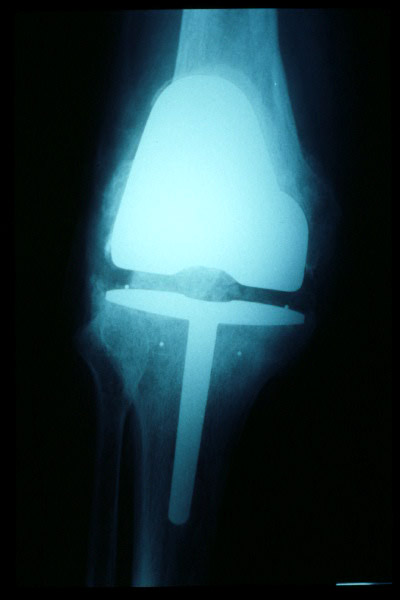

Prótesis completa de rodilla. Situación postquirúrgica.

Prótesis completa de rodilla. Situación postquirúrgica. Lateral.

Prótesis completa de rodilla.Lateral.

Prótesis completa de rodilla. Frontal.

Prótesis completa bilateral de rodillas.

Prótesis completa de rodilla. Perfil.

Prótesis completa de rodilla. Frente.